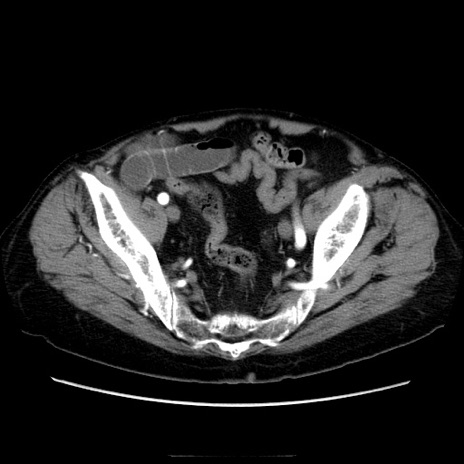

症例21(横断像)

【症例】70歳代男性

【主訴】腹痛

【現病歴】肝硬変・肝細胞癌にてかかりつけの方。約9時間前に食後より腹痛出現。症状が徐々に増悪し、嘔吐出現したため来院。

【既往歴】肝硬変、肝細胞癌(RFA、TACE後)

【身体所見】意識清明、表情苦悶様、BT 36℃、BP 129/78mmHg、P 88bpm、SpO2 97%(RA)、右上腹部から心窩部にかけて圧痛あり、反跳痛なし、筋性防御あり。

【データ】WBC 5800、CRP 0.16